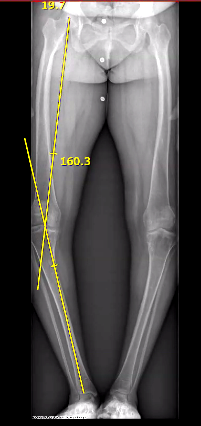

Accurate assessment of lower limb alignment is crucial for diagnosing and treating musculoskeletal conditions. It helps identify any misalignment in the natural positioning of the hip joint, knee, and ankle by calculating HKA angle (Hip knee Ankle angle). This is especially important when evaluating a patient's recovery after major surgical procedures such as total knee or hip replacement, which can significantly affect posture and gait. Such misalignments may impair a person’s ability to walk properly, as the body can no longer evenly support their weight.

Traditional assessment methods, such as full-length X-rays, though reliable, expose patients to radiation and require specialized equipment. This makes them less practical for frequent evaluations or in remote healthcare facilities that have limited resources.

Radiographic Imaging

Fig. 1: Radiographic imaging of the hip-knee-ankle angle on conventional scanograms (A) and in EOS (B)